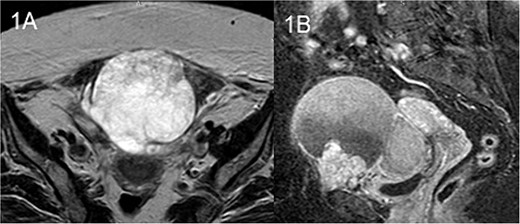

The patient underwent an MRI which revealed a large cystic pelvic mass, measuring 10.3 x 9 x 11.1 cm, with septations and solid component in contact with the anterior abdominal wall, and the bladder as well (Fig. 1). There was no evidence of vascular invasion from the mass. A colonoscopy followed in order to exclude the involvement of the colon and rectum, which was normal.

MRI T2 axial (A) and sagittal (B): solitary mass in contact with rectus abdominis.